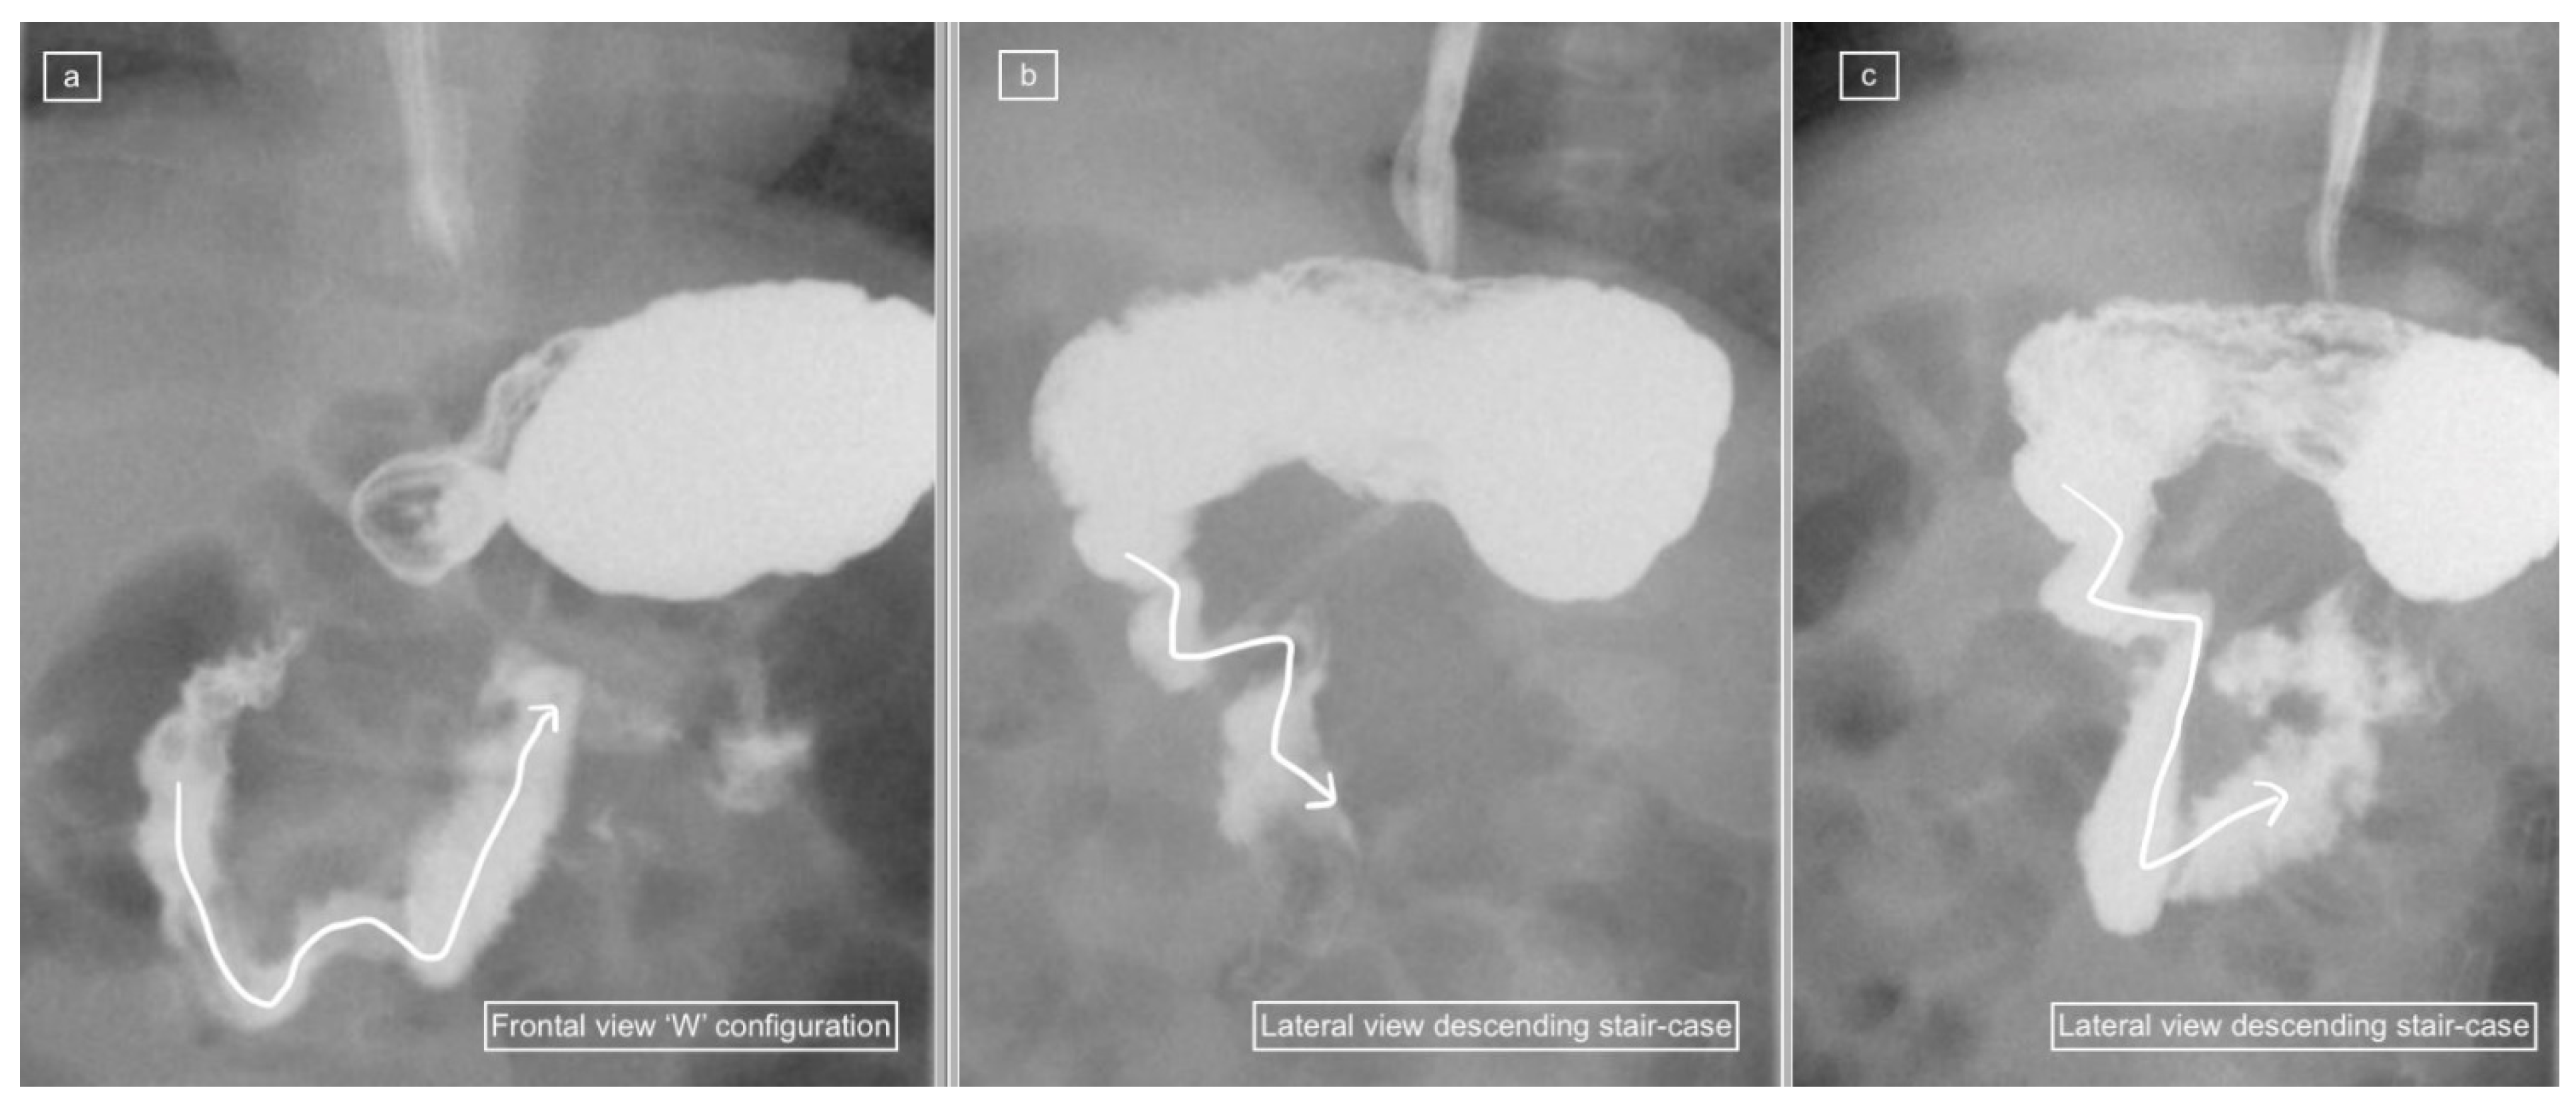

Figure 2.

(a–c): Representative images captured during an UGIS in a 3-month-old boy demonstrating duodenum redundum on the frontal and lateral views. (a) Frontal view demonstrates redundancy of the duodenal loop which instead of having a C-loop configuration now has a W-loop configuration (white line) and a normal position of the duodeno-jejunal flexure (immediately distal to the end of the arrowhead). (b) Early and (c) later lateral views captured prior to the frontal view in (a) demonstrate a descending staircase configuration of D1 and D2 oriented posteriorly, after which the duodenum ascends in the retroperitoneal position, leading up to the duodeno-jejunal flexure in the expected normal position at the same height as D1, before coursing anteriorly.

Figure 3.

(a–d): Representative images captured during an UGIS in a 49-day-old boy demonstrating duodenum redundum on the frontal and lateral views, with the order of images representing the order that the images were captured through multiple repositioning maneuvers. (a) Lateral view demonstrating the descending staircase sign oriented posteriorly from D1 and involving D2. (b) Frontal view demonstrating the W-loop configuration of duodenum redundum made up here by D2 and D3. (c) Repositioning in the lateral view demonstrates the posterior position of D3 inferiorly and that the ascending D4 remains posterior. (d) Return to the frontal position now demonstrates the contrast outlining the duodeno-jejunal flexure (DJ) just slightly inferior to D1 and to the left of the spine—considered within the normal range allowing for patient positioning.

Figure 4.

(a,b): Representative images captured during an UGIS in a 2-month-old boy demonstrating duodenum redundum on the lateral and frontal views. (a) Lateral view demonstrates a descending staircase configuration of D1 and D2 oriented posteriorly, after which the duodenum remains (D3) and ascends (D4) in the retroperitoneal position, leading towards the duodeno-jejunal junction (not shown here). (b) Frontal view demonstrates redundancy of the duodenal loop which, instead of having a C-loop configuration, has a W-loop configuration, made up of D2, D3 and D4 (white line) and a normal position of the duodeno-jejunal flexure (DJ).